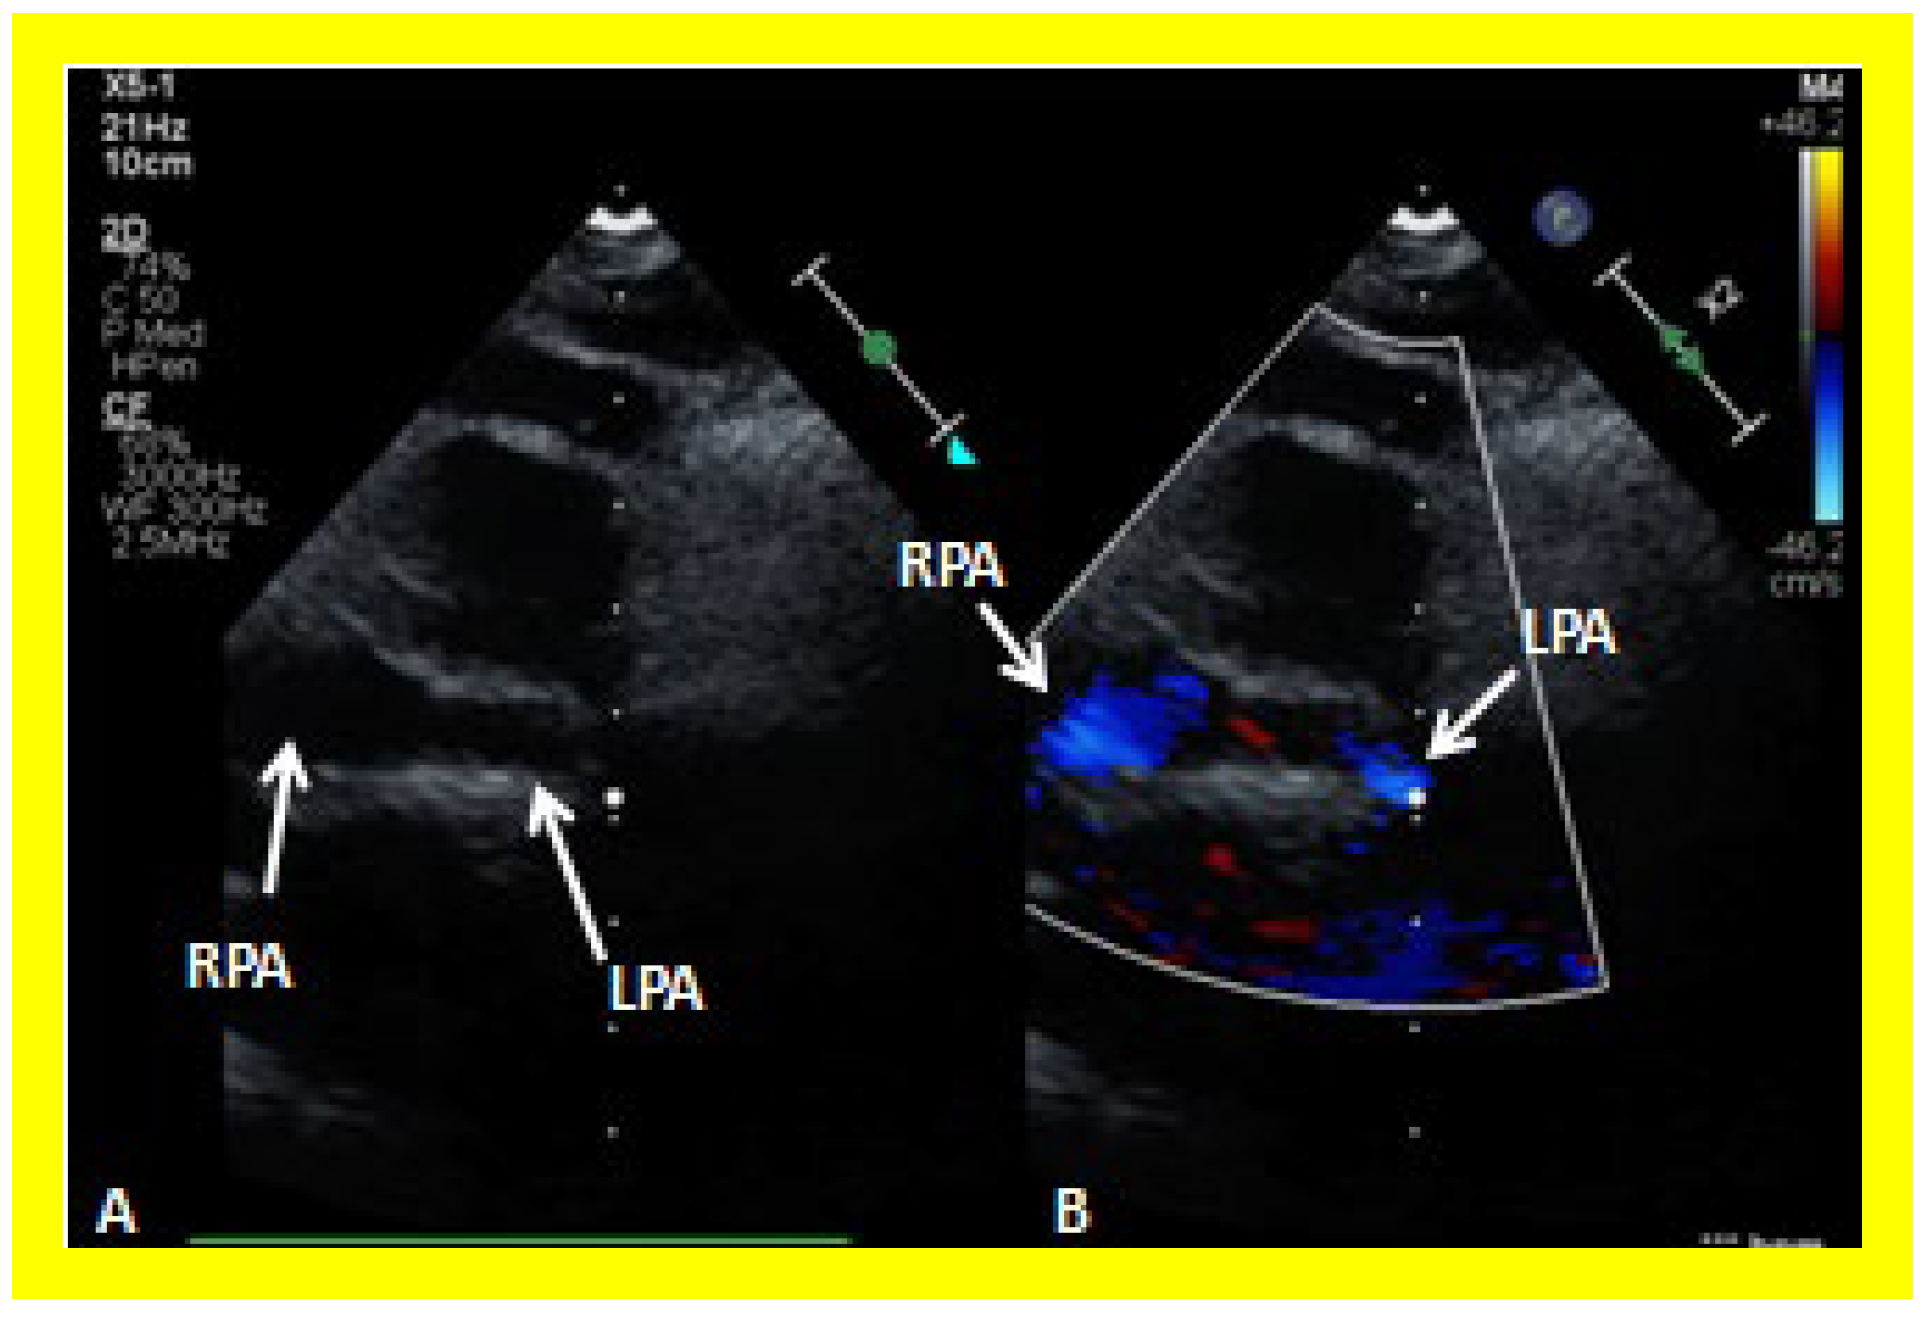

Figure 26. (A,B) Selected video frames from suprasternal notch view demonstrating bidirectional Glenn shunt. In (A), the right (RPA) and left (LPA) pulmonary arteries are shown by 2D. The superior vena cava (SVC) was not clearly seen. In (B), the SVC is shown emptying into the RPA by color Doppler (B). The LPA did not show color flow because it was in a different plane of imaging than RPA, but is seen by 2D (B). (C) Low Doppler flow velocity across the Glenn shunt indicates unobstructed flow.

Following bidirectional Glenn, the LV size is likely to decrease (normalize) and LV should maintain normal systolic function. This is because of decreased LV volume overload following bidirectional Glenn and the removal of aorto–pulmonary shunt. The 2D imaging of the bidirectional Glenn is difficult to accomplish, but color flow imaging (Figure 25A, Figure 26B, and Figure 27B) from a suprasternal notch or high parasternal views will help image the bidirectional Glenn. Low pulsed Doppler velocity across the superior vena cava (SVC)–PA junction (Figure 25B and Figure 26C) would indicate no obstruction. Turbulent and high velocity Doppler flow suggests the obstruction of the bidirectional Glenn shunt. The size of the branch PAs may be assessed with a combination of 2D and color flow imaging (Figure 26, Figure 27 and Figure 28).